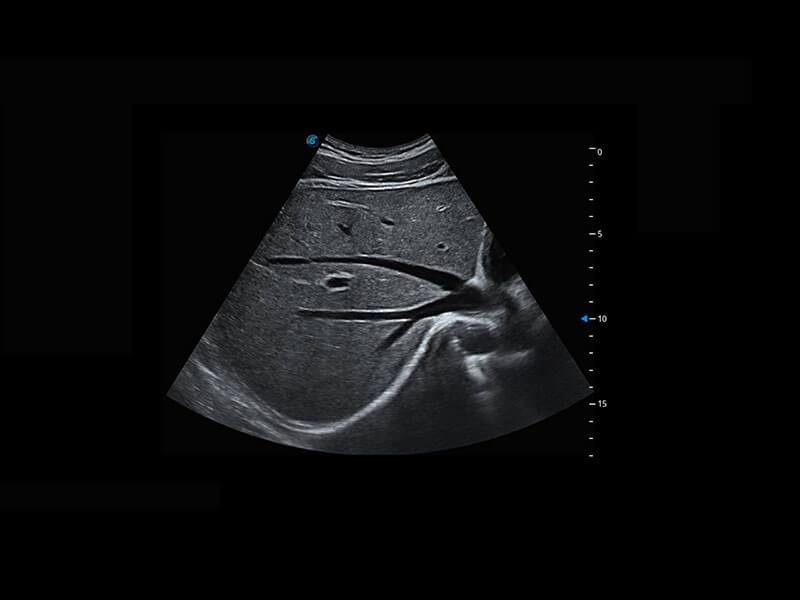

盆底超声

P60为盆底超声检查提供应用方案,多种腔内及腹部容积探头提供从二维、三维到四维的优异图像品质,实时快速三维容积数据获取,专业的测量工具包等人性化设计,为超声医生诊断提供有力保障。

Lev.Hiat A-r: 16.33 cm2

Lev.Hiat H-r: 53.70 mm

Lev.Hiat W-r: 43.96 mm

Lt-LUG-r: 24.16 mm

Rt-LUG-r: 19.94 mm

S-Pelvic

能够简化盆底检查的操作流程,可在二维模式及三维成像模式下实现一键自动提取出标准切面、自动识别当前切面、自动测量,提升盆底检查的高效性,同时也能让青年医生快捷的获得准确的检查结果。